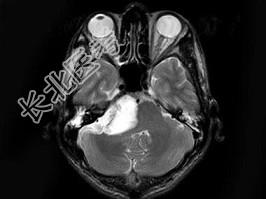

- 单项选择题男,38岁, 头痛半年余,MRI检查如图, 最可能的诊断是 ( )

A、听神经瘤

B、三叉神经瘤

C、表皮样囊肿

D、皮样囊肿

E、未见异常